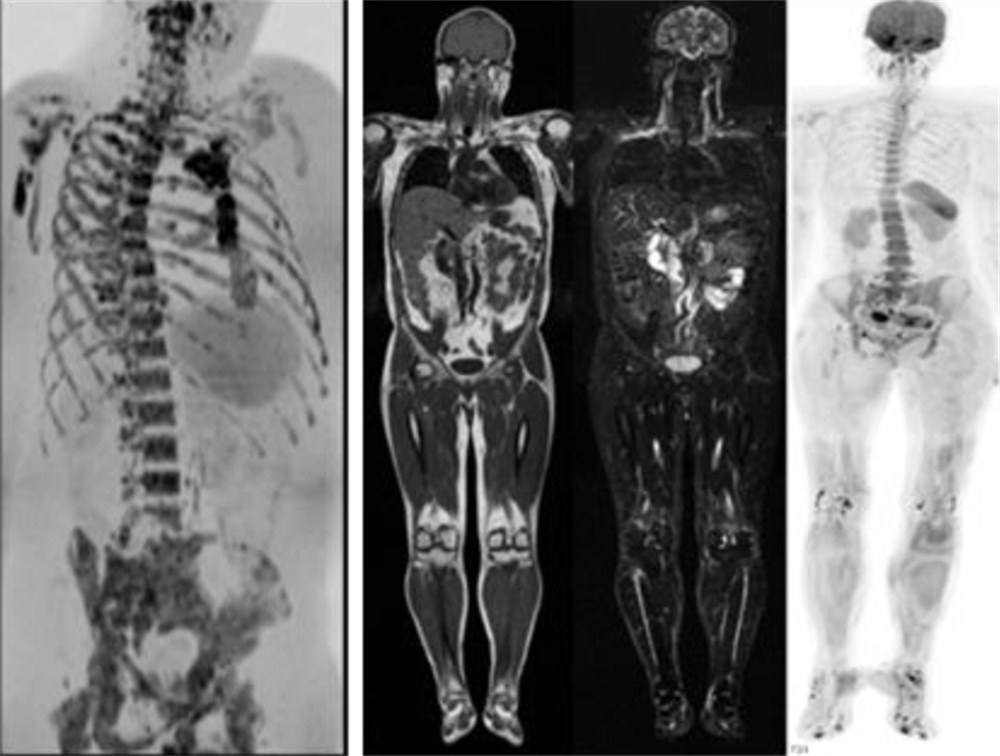

在全身弥散加权成像的同时,可进行磁共振全身扫描,增加肿瘤检出敏感性。

临床应用范围:寻找恶性肿瘤原发灶;恶性肿瘤分期;全身转移灶筛查;淋巴结转移筛查;术后放化疗疗效监测;恶性血液肿瘤疗效观察;体检与肿瘤筛查。